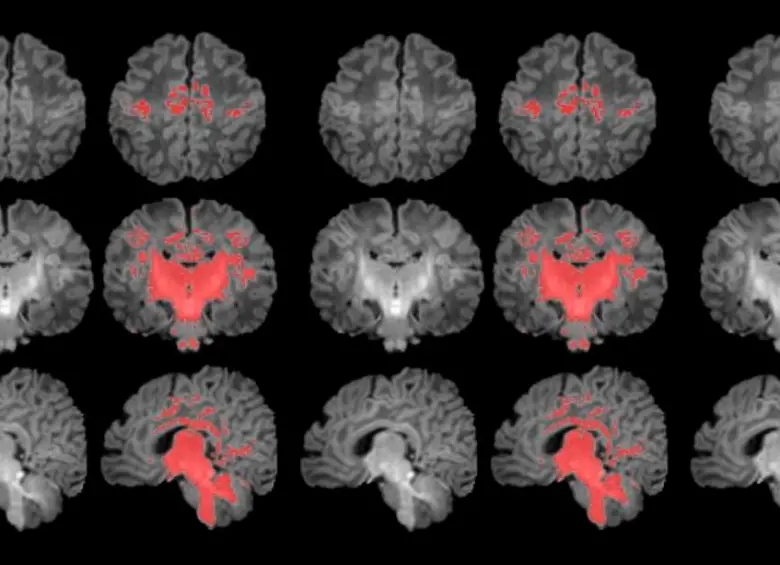

• Es el primer estudio que mide con resonancia magnética la mielinización cerebral de los recién nacidos. FOTO Pujol et al., 2025 | ISGlobal

Es el primer estudio que mide con resonancia magnética la mielinización cerebral de los recién nacidos. FOTO Pujol et al., 2025 | ISGlobal

Resonancia magnética en el primer mes de vida

Para llevar a cabo el estudio se reclutó a mujeres embarazadas en seguimiento en el Hospital Clínic Barcelona, el Hospital de Sant Pau y el Hospital Sant Joan de Déu. Se monitorizaron los niveles de contaminantes atmosféricos a los cuales estaban expuestos durante la gestación y, después del parto, se seleccionó a 132 recién nacidos. A estos se les realizó una resonancia magnética antes de cumplir el primer mes de vida para observar el grado de maduración cerebral según sus niveles de mielinización.

Los resultados muestran una correlación clara entre una mayor exposición materna a PM2.5 durante el embarazo y una menor mielinización en el cerebro de los recién nacidos.